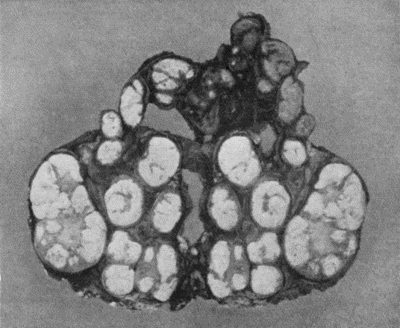

| 72. | Sacculated Aneurysm of Abdominal Aorta | 304 |

| 73. | Radiogram of Innominate Aneurysm after Treatment by Moore-Corradi method | 309 |